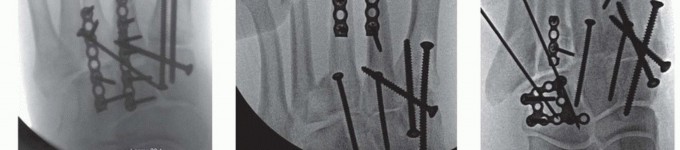

FIG 4

• CT scan showing displacement through second tarsometatarsal and intercuneiform articulations (

A

) and intra-articular fractures of navicular and cuboid (

B

,

black arrows

) in a different patient.